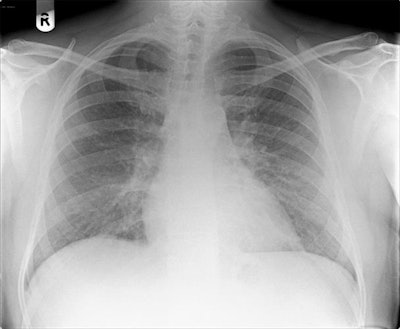

Chest radiograph reported as normal. Note the diffuse ground-glass shadowing in all zones. Images courtesy of Dr. Patrick Liu-Shiu-Cheong, Dr. Owen Dempsey, and BMJ Case Reports 2019."Our patient's CXR [chest x-ray] report was initially reported as normal (although we disagreed)," the authors wrote. "He subsequently had a CT pulmonary angiogram with high-resolution reconstruction (to exclude pulmonary thromboembolic as well as interstitial lung disease), reported as showing a ground glass, mosaic pattern in both lungs, with borderline enlarged hilar nodes, presumed reactive."